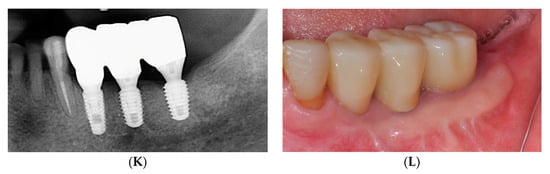

2.1. Surgical Procedures of the Simplified Free Gingival Graft Using Fixation Tacks (sFGG)

2.2. Case